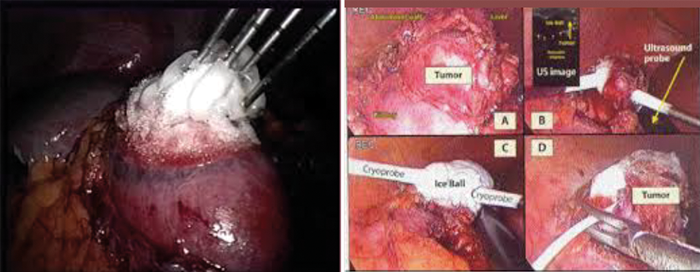

Figure 6 (left): Multiple probes used to achieve satisfactory coverage of the tumour.

Figure 7 (right): Intraoperative ultrasound used to identify the tumour margins to aid probe placement.

Renal cryoablation can be performed laparoscopically or percutaneously under ultrasound, CT or MR guidance [Figures 4-7]. Tissue injury occurs by both cellular damage caused during the freezing phase and also by reperfusion injury during the thawing phase; both of which lead to coagulative necrosis and fibrosis [20]. This is caused by the deposition of intracellular and extracellular ice crystals, an event that leads to the disruption of the cell membrane, intracellular structures and the local microvasculature.